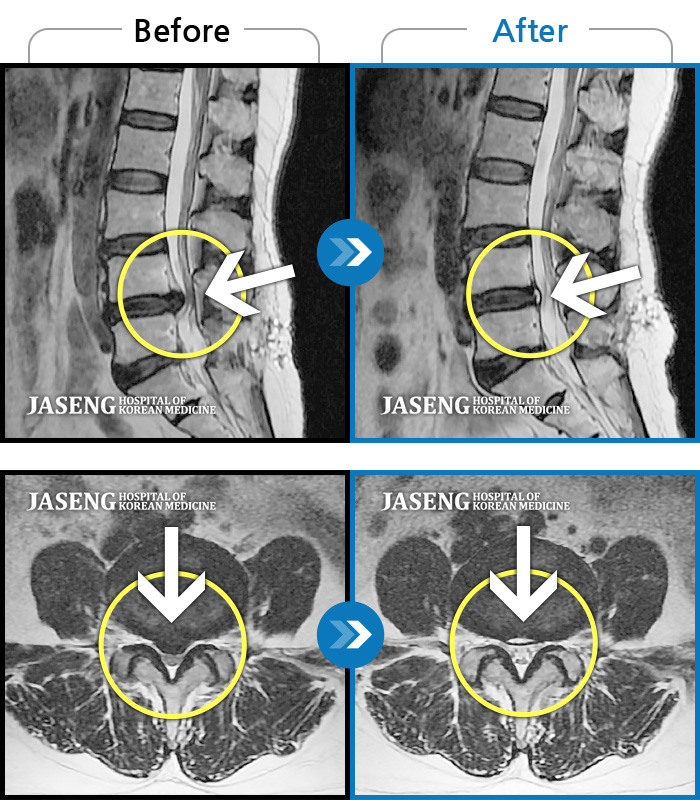

[뱸] 19.11.28~25.05.06